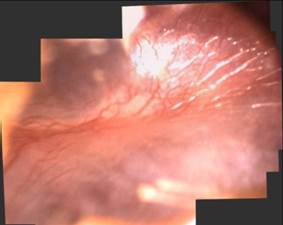

- to create enhanced composite images of the eardrum using novel computer vision and image stitching of otoscopic video clips gathered during patient examination, and

Computer-assisted image analysis (CAIA) of composite images of the eardrum will generate a likely diagnosis and level of confidence for each patient, such as an 80 percent likely diagnosis of AOM. Previous studies have utilized CAIA but have been limited in focus to determining or ruling out AOM. In contrast, the Autoscope developers’ goal is to assist in point-of-care diagnosis of a number of ear pathologies, including AOM, middle ear effusion (non-infected fluid), cholesteatoma (skin cyst in the ear), eardrum perforation and eardrum retraction. Clinicians also will be able to search other cases from the well-annotated database and retrieve relevant eardrum images for comparison and diagnostic support.